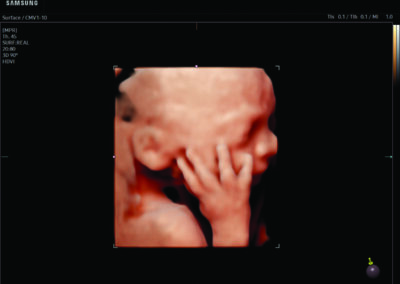

Comprehensive, advanced and expert MFM care for high-risk pregnancies

- Fetal anomalies